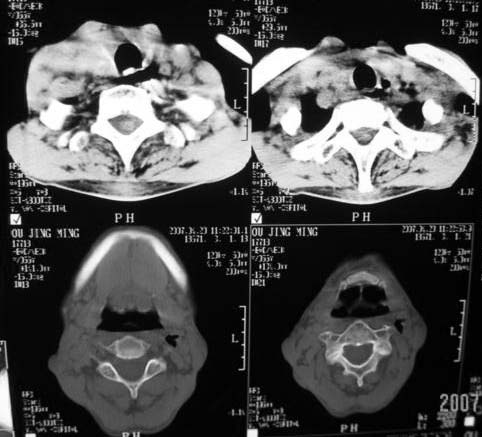

以下是引用dyqct在2007-4-20 16:19:00的发言:[br]考虑:1、左侧梨状窝区破裂伴左颈深、浅部气肿。[br] 2、右侧甲状腺区血肿(请追问病史是否伤及右颈部)。[br] 3、建议病情稳定后增强扫描除外右侧甲状腺腺瘤。